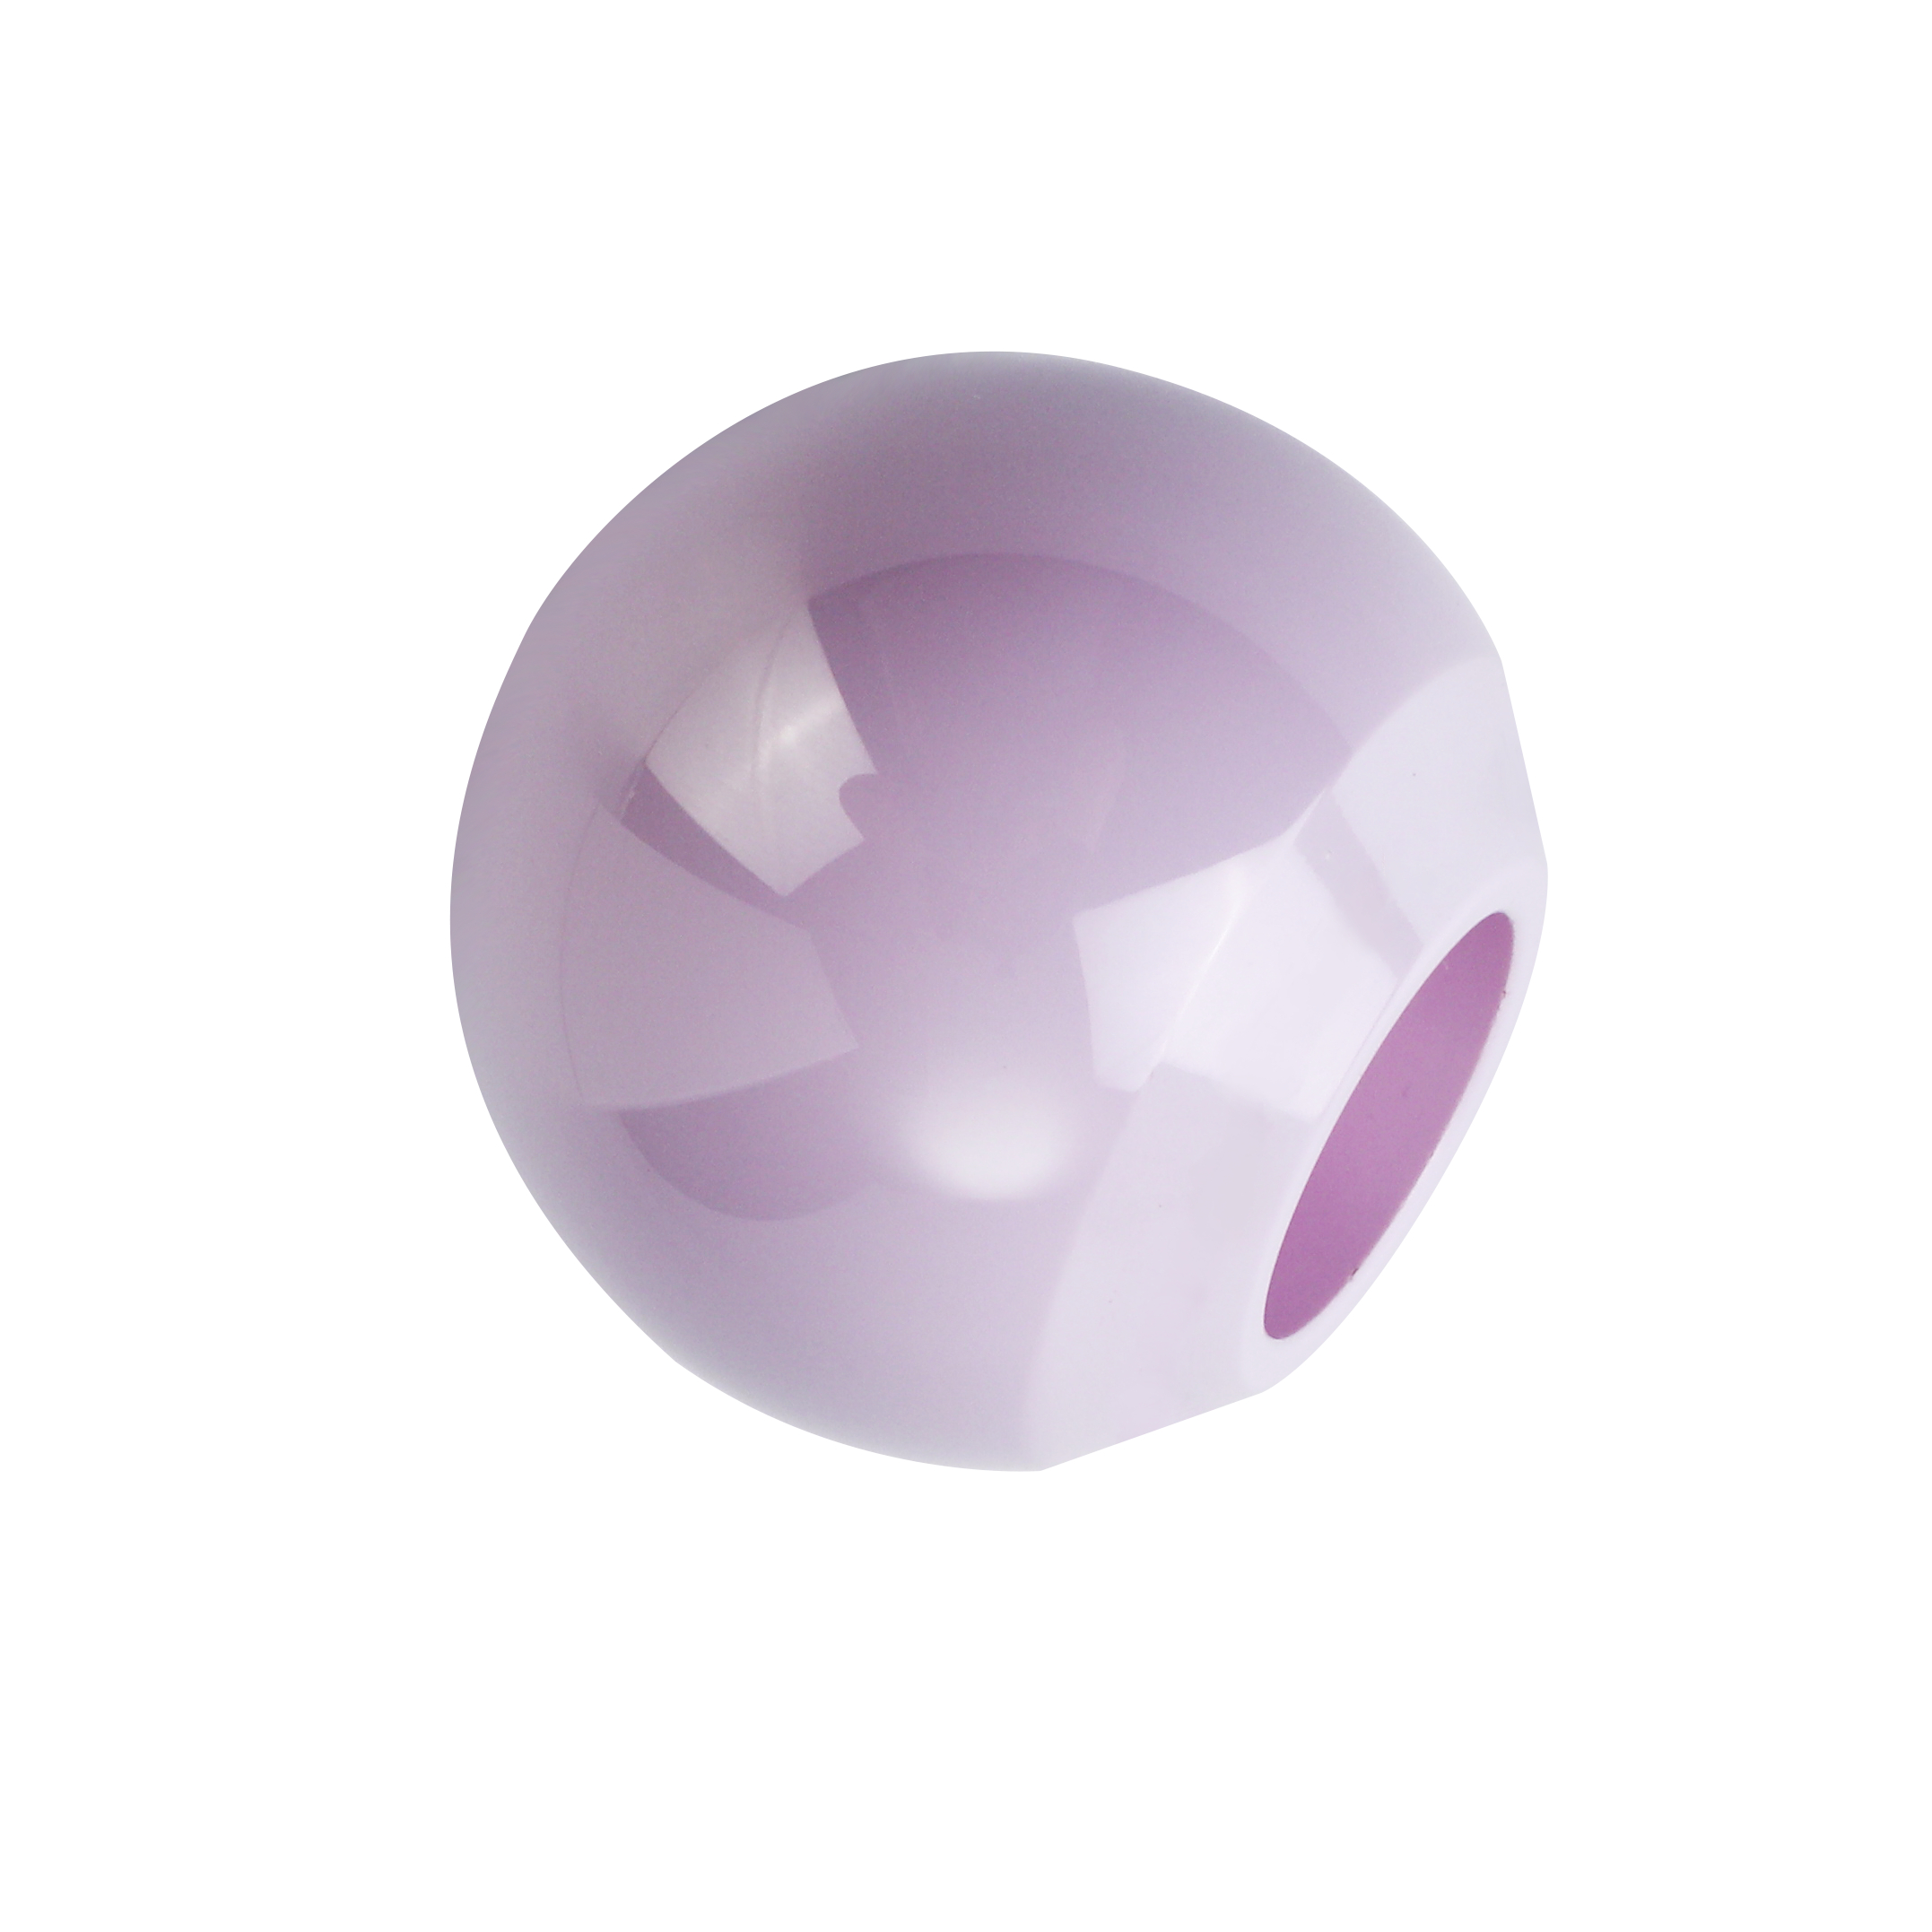

Artica® G5 Zirconia Ceramic Heads

-

Artica G4 ZTA Ceramic Heads

-